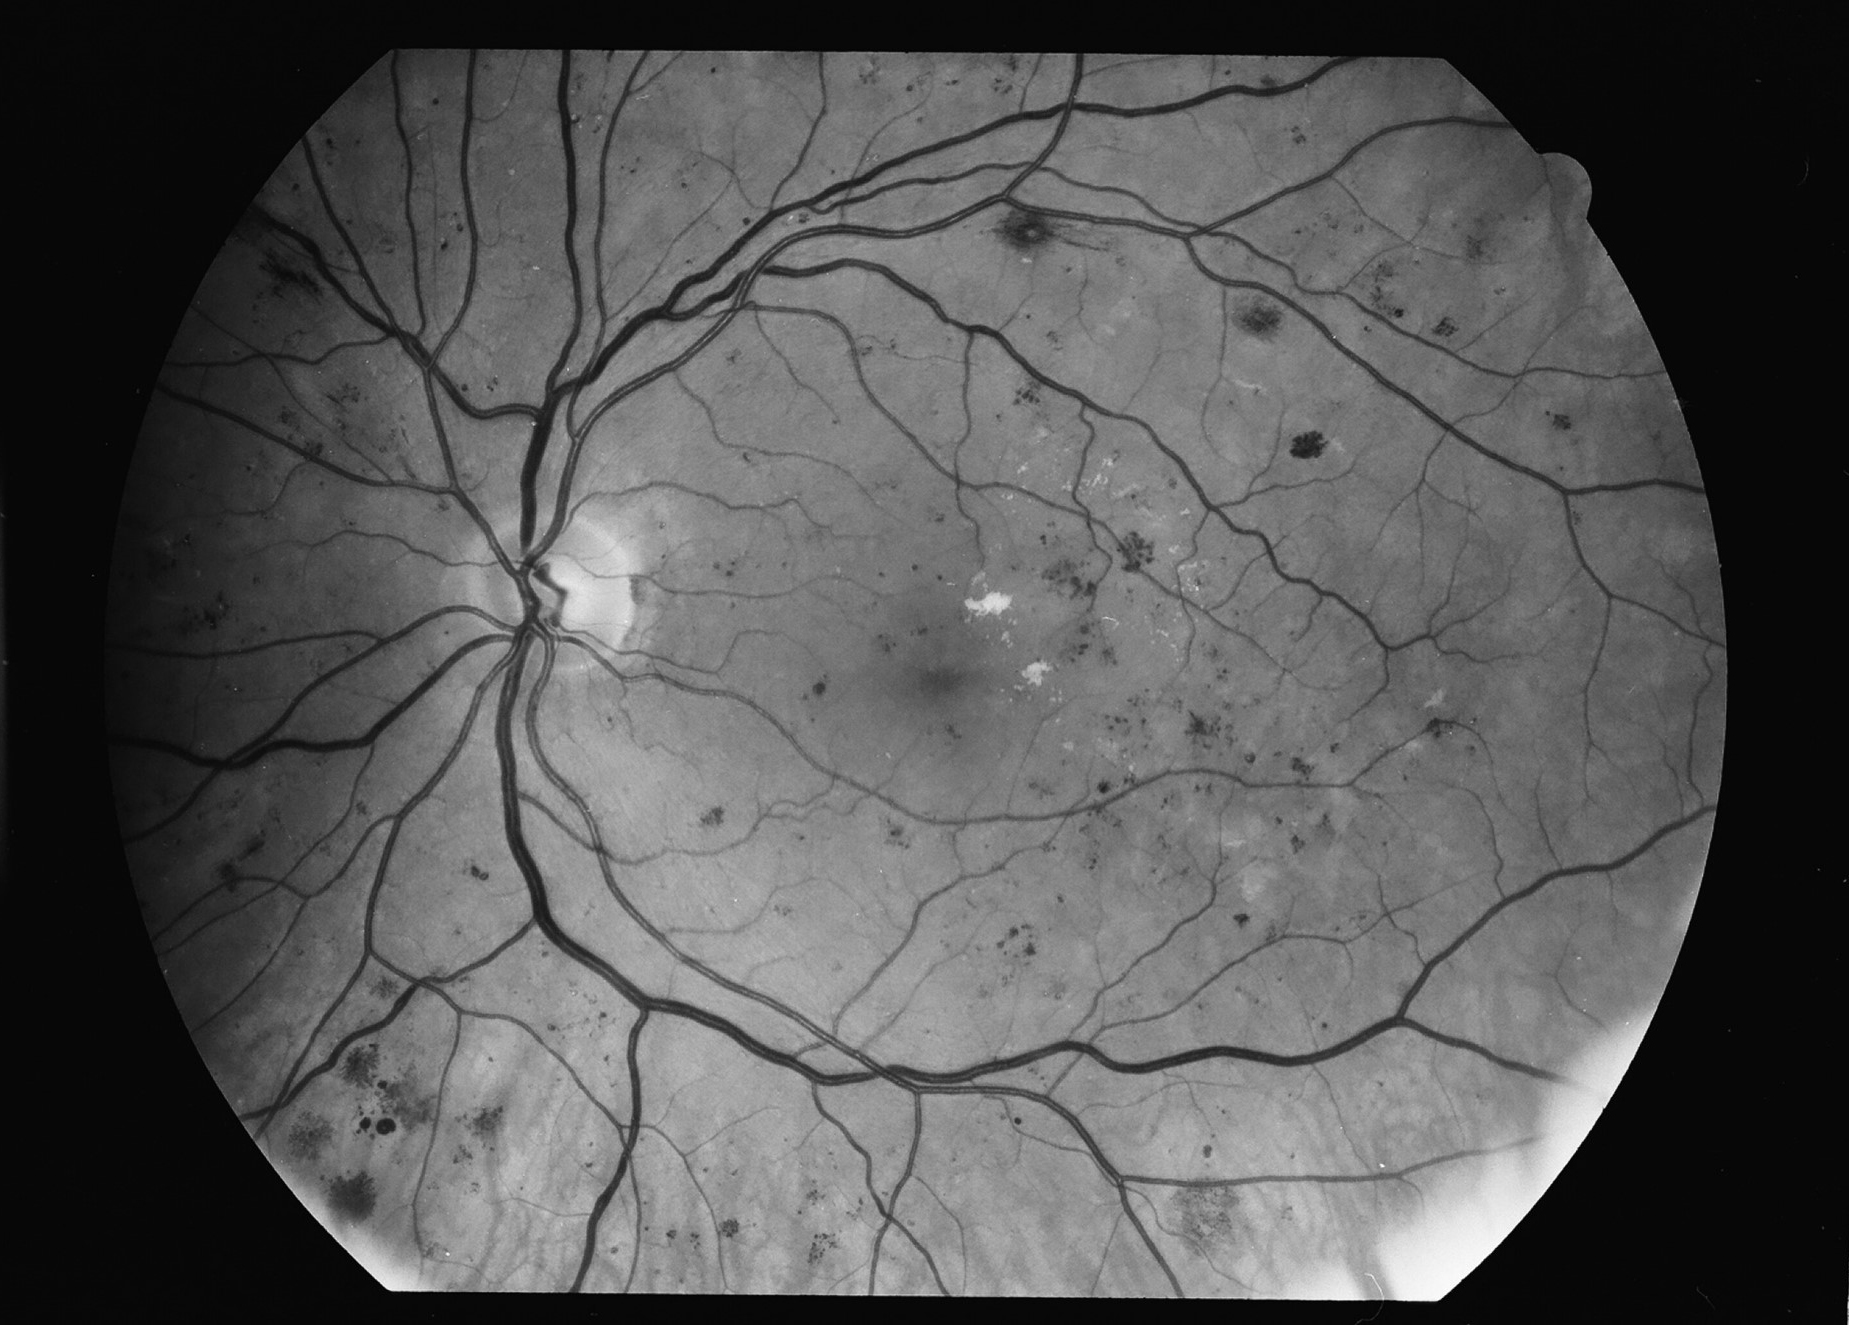

Kuva 6.

Diabetes, taustaretinopatia, oikea silmä. Mikroaneurysmia, mikroinfarkteja, vuotoja ja lipidieksudaattia.